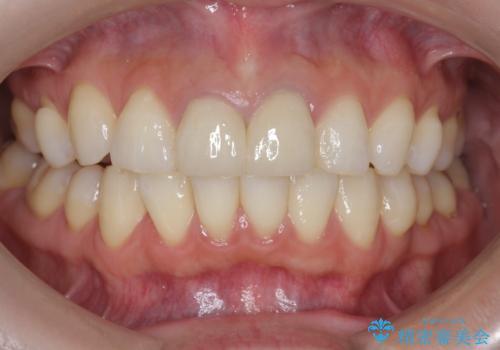

前歯が疼く セラミッククラウンのやり替え

- 「幼少期に転んで治療した前歯がうずく、疲れると膿が出る。」と治療を希望され来院されました。

X線写真検査に加え圧痛、打診痛が認められたため、慢性根尖性歯周炎と診断し、根管治療から行うセラミック治療を計画します。

今回は根尖性歯周炎に対する根管治療を行ったことで症状は改善し、快適に食事ができる状態へと改善しました。